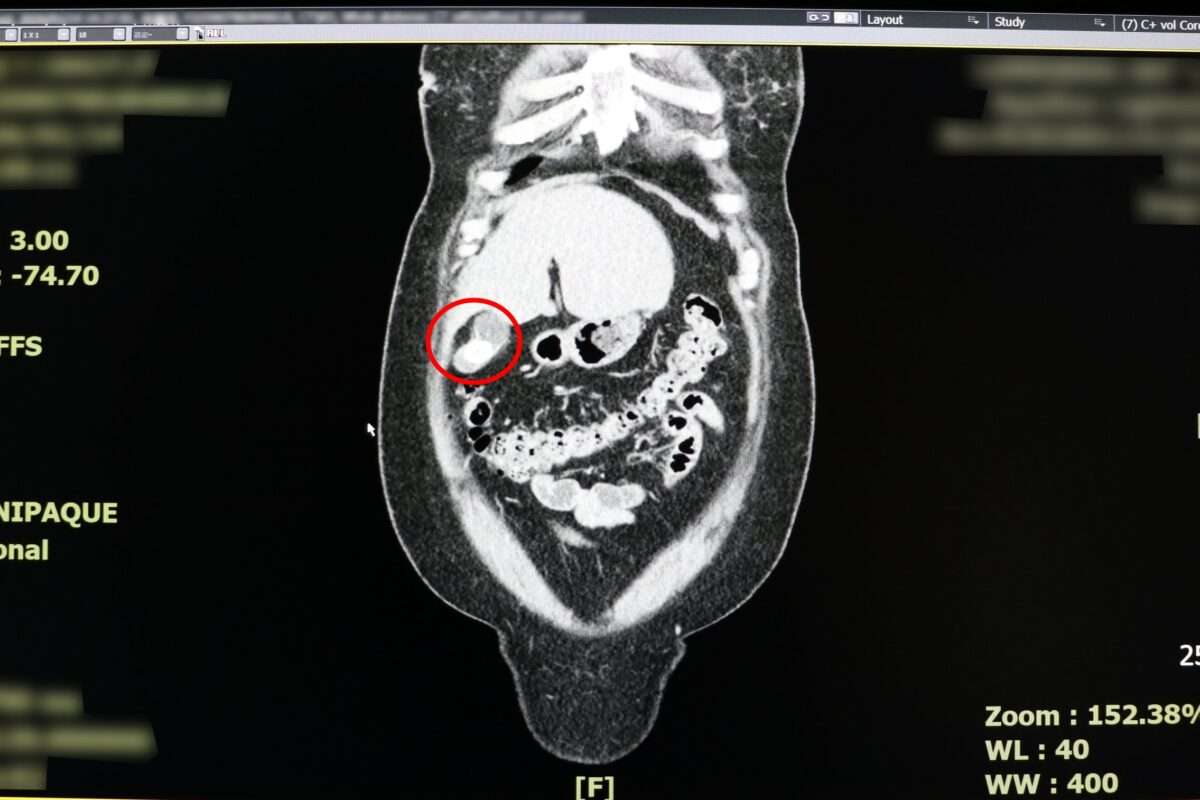

反覆上腹部疼痛時,別再以為只是胃病,當心是「體內未爆彈」膽囊炎作祟。一名38歲女性日前因持續2天劇烈上腹痛,先後到診所與地區醫院就診,皆被診斷為胃炎,服藥與打止痛針仍未改善,求診聯新國際醫院急診室,經醫師朱海慶詢問病史與電腦斷層檢查,會診一般外科醫師張堯任,確診為急性膽囊炎。

病患就醫時已出現發燒,白血球與發炎指數攀升的情況,張堯任建議應盡快手術。病患考量自身工作需頻繁搬運重物,且希望快速復工,選擇單孔達文西手術切除膽囊,術後當天即可下床走動並正常飲食,隔天返家休養,迅速重返職場。